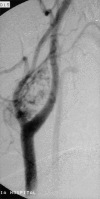

Pediatric endocrine tumors are rare but have fairly characteristic presentations. We describe an approach to diagnosis and management of five of the most common presentations including gonadoblastoma, paraganglioma, medullary thyroid cancer, adrenal cancer, and pituitary adenoma. Genetic testing can aid in the early detection and prevention and management of tumors in patients and in other family members.